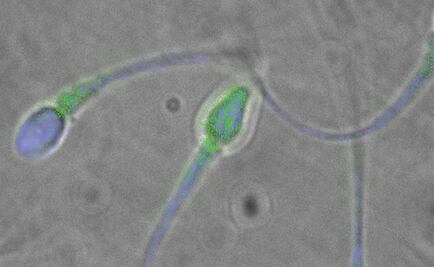

Al exponer muestras de un glioblastoma humano (tumor de crecimiento rápido) en un plato con un cultivo de virus Zika, éste destruyó las células madre del cáncer